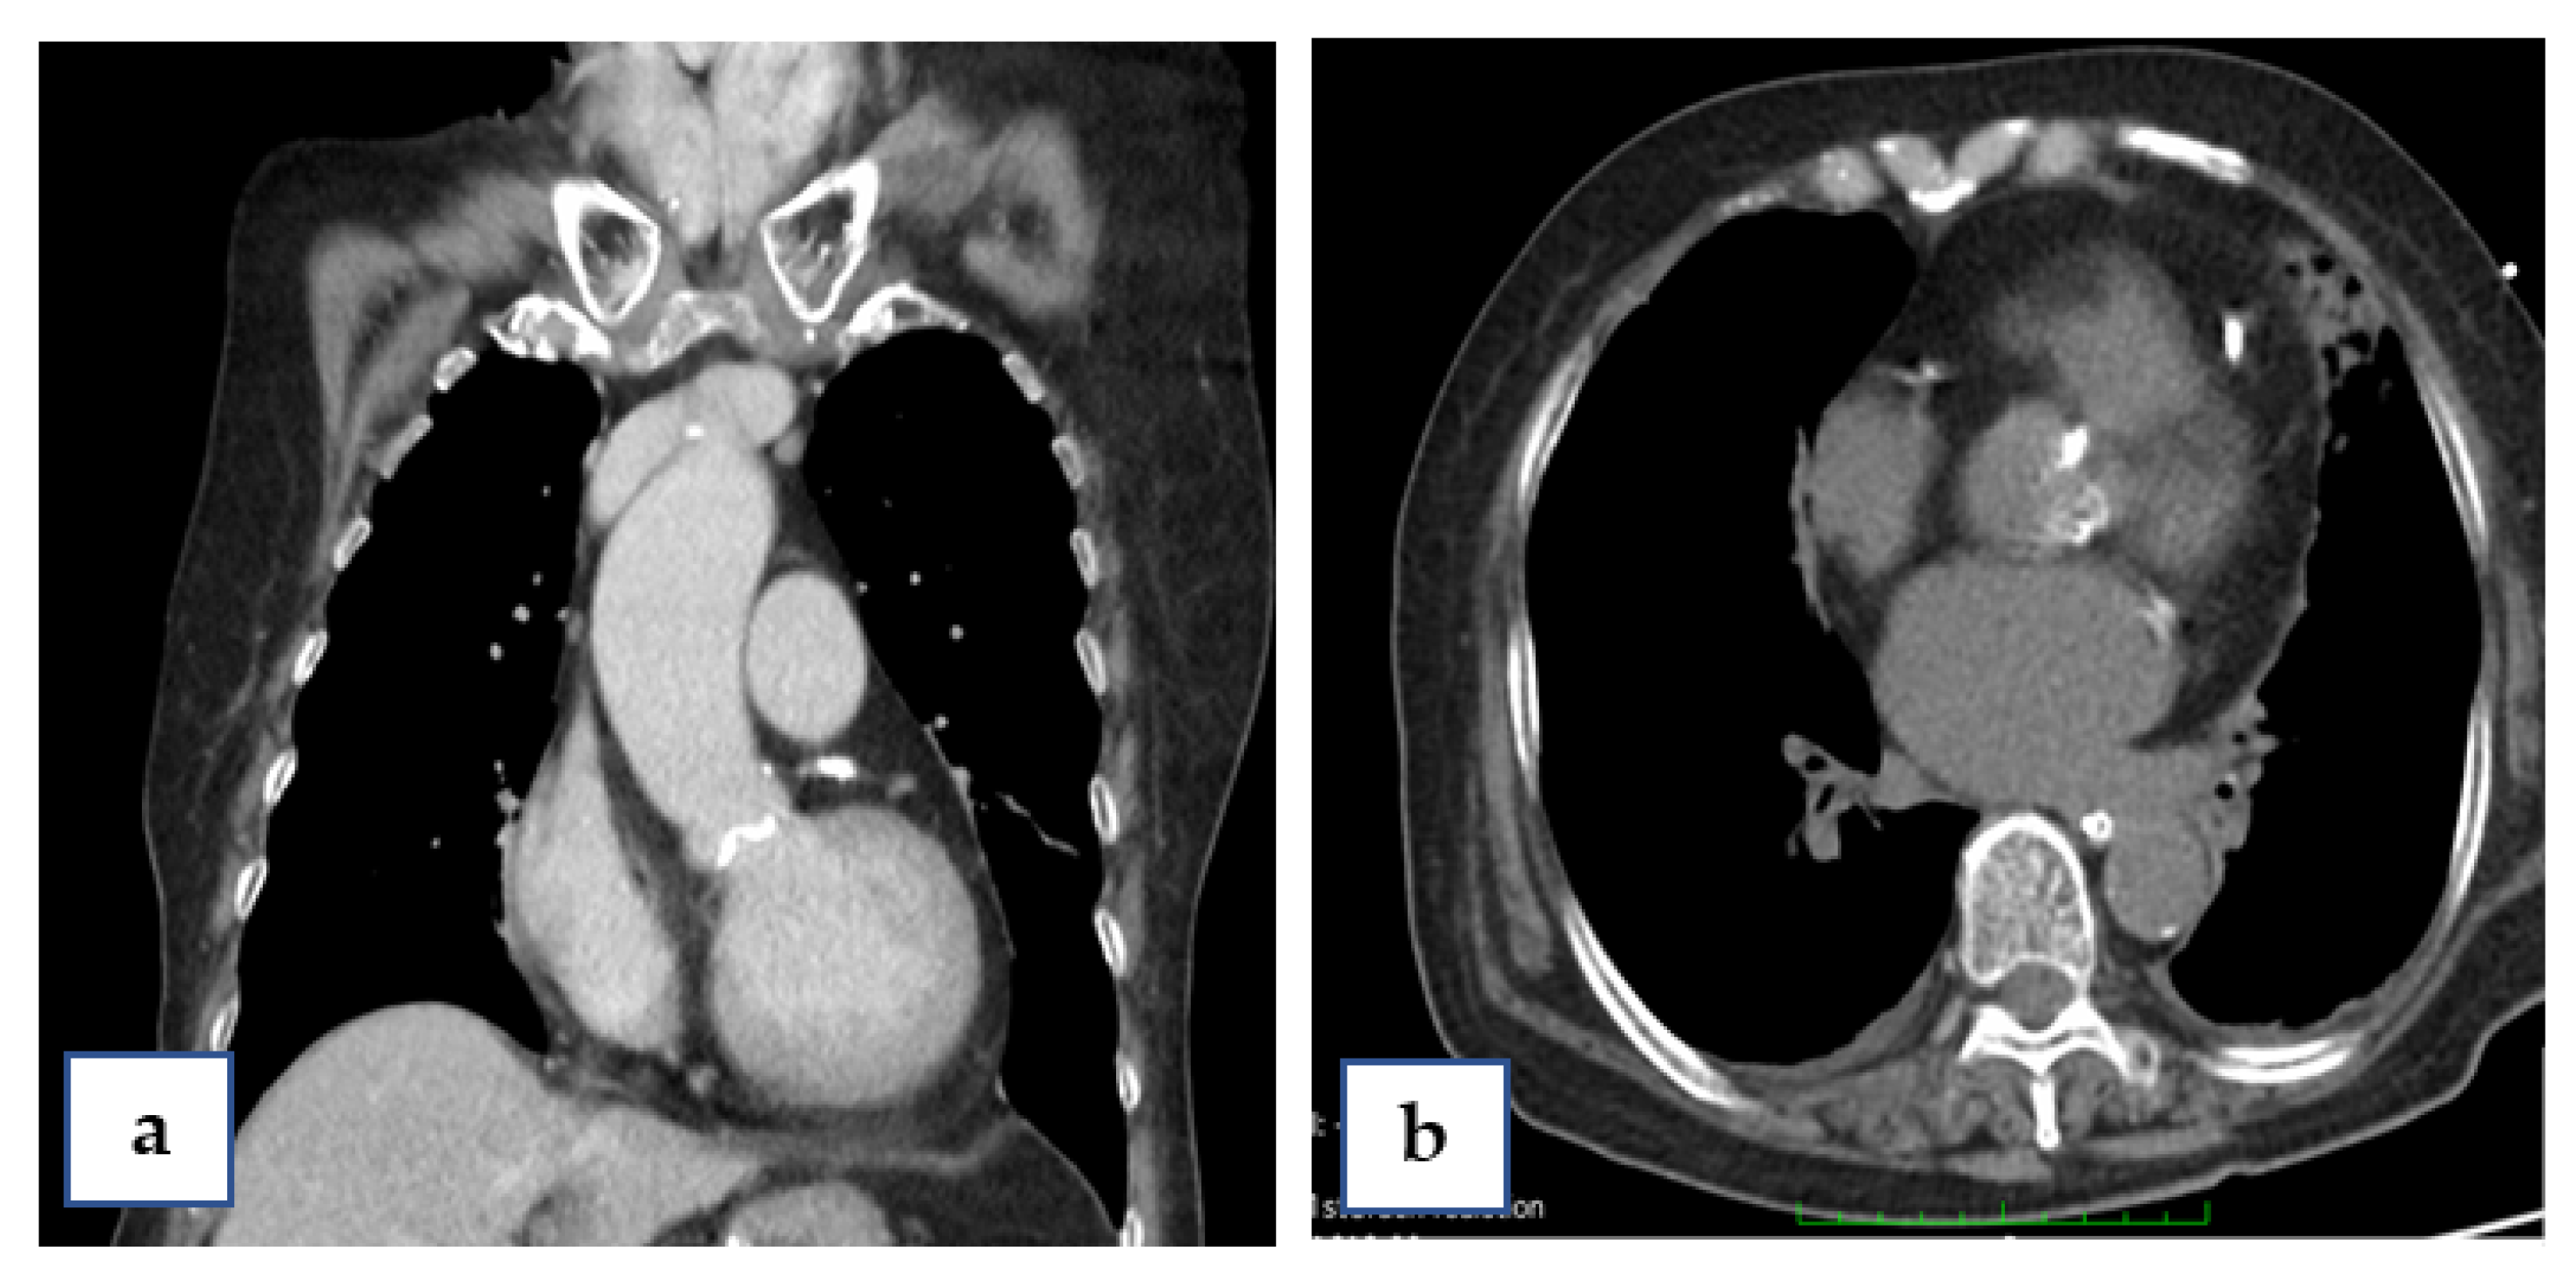

An 88-year-old female patient (height = 160 cm, body weight = 59 kg, BMI = 23) had increasing shortness of breath and visited our emergency department. Her past history included bronchial asthma and hypertension with regular treatment at our hospital. Initially, a mild elevated Troponin-I = 1.58 ng/mL (normal value, <0.16) was measured. Coronary angiography revealed three-vessel-disease: left anterior descending artery (LAD), middle-segment with long lesion up to 90% stenosis; left circumflex artery (LCX), distal-segment with chronic total occlusion; and right coronary artery (RCA), middle-segment with 40% tandem lesions (Figure 1a–c). Critical aortic valve stenosis (AS) with a mean pressure gradient (PG) of 43 mmHg was additionally diagnosed. The estimated aortic valve area (Gorlin equation) was 0.6 cm2. Her left-ventricular ejection fraction (LVEF) was about 58%.

Coronary artery bypass graft (CABG) and surgical aortic valve replacement (SAVR) or percutaneous coronary angioplasty (PCI) and TAVI were suggested to her family. They said they needed a family meeting to discuss it. However, the next day after the coronary angiogram, her dyspnea was more serious and her blood saturation of oxygen was down to 60%. So, she was intubated with mechanical ventilation. Based on her co-morbidities and old age, her logistic Euroscore was 25%, which is high risk (>13%). PCI and TAVI were preferred. PCI was performed next day of intubation, smoothly with two drug-eluting-stents (2.75 mm × 28 mm and 2.5 mm × 28 mm Xience, Abbott, Chicago, IL, USA) in the LAD (Figure 1d). The computed tomography (CT) showed moderate calcification of the aortic valve (Figure 2). Her family requested to wait for an important son coming back from abroad and for her to then receive TAVI. So, she was kept intubated with mild sedation. The patient’s renal function was within the normal limit: blood creatinine was 0.59 mg/dL (normal range 0.50–0.90 mg/dL) before PCI and 0.67 mg/dL after PCI; her hemodynamic condition was stable before and after stent implantation until the night prior to TAVI; four days after PCI, the patient’s vital signs became unstable. Atrial fibrillation (AF) with fluctuated ventricular response and arterial hypotension were noted. Inotropic agent (dopamine 8 μg/kg/min) was given. Upon arrival in the hybrid operation-room, tachycardia atrial fibrillation with about 110 beats per minute bpm was noted. After the induction of general anesthesia, her heart rate dropped to about 60 bpm and she subsequently went into cardiac arrest. Cardiopulmonary resuscitation (CPR) was therefore initiated for about 15 min. A veno-arterial (VA)-ECMO (Capiox, Terumo (Tokyo, Japan; with venous sheath 21 French and arterial sheath 16.5 French) was installed in her left femoral side. Ventricular tachycardia (VT) and ventricular fibrillation (VF) occurred, and 200 joule cardioversion was done twice to restore sinus rhythm. Urgent-TAVI was performed with a 25 mm × 4 cm ZMED2 balloon for pre-dilatation and a 31 mm CoreValve Evolut (Medtronic, Dublin, Ireland) implanted (Figure 3). After the TAVI procedure, she was transferred back to ICU. Despite the sinus rhythm being restored, her LVEF was 22%, which was due to cardiac arrest. We used Levosimendan-therapy and then her LVEF rose to 40%. Pulmonary hemorrhage occurred two days later on ECMO. Her activated partial thromboplastin time (APTT) reached 112.2 s (normal range 24.3–32.7 s). Heparin was held for hours and 10 units of packed red blood cells (RBC) and 4 units and fresh frozen plasma (FFP) were transfused. Then, her APTT was maintained between 50 and 60 s.

Figure 1. Coronary artery lesions of the patient. (a) Cranial view of coronary angiogram (CAG) revealed diffuse severe stenosis of the left anterior descending artery (LAD). (b) Caudal view of CAG shows total occlusion of the left circumflex artery (LCX). (c) CAG of the right coronary artery (RCA). (d) After percutaneous angioplasty (PCI) with two stents for LAD.